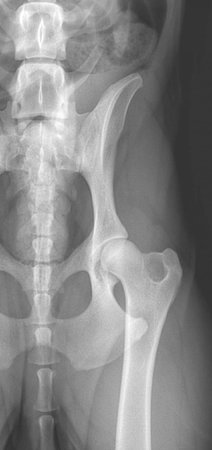

DR. PETRA OST,DR.MED.VET, DAVCS DMV: Justus-Liebig University, Giessen, Germany Internship: Justus-Liebig University, Giessen, Germany Residency: Ohio State University AVCS Certification: Staff Surgeon at MedVet Cleveland Founded one of the first veterinary specialists offices in the Portland area Founded Mt. Hood Veterinary Specialists, which joined with SEPAH in '07. Dr. Ost was also one of the first veterinary surgeons to perform the TPLO in the US ('95). She now lives in the Damascus with her husband (Dr. Don Kennard, Medical Director of VCA-12 Mile Animal Hospital), their two children, 2 dogs, 1 cat and 3 horses. Her surgical interests include a wide variety of soft tissue, orthopedic and neurological surgeries.